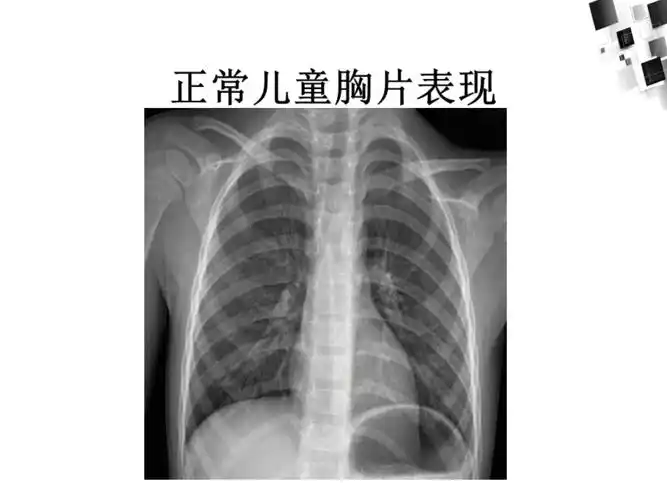

中医院放射科带您解读小儿肺炎

儿童常见肺部感染ppt课件